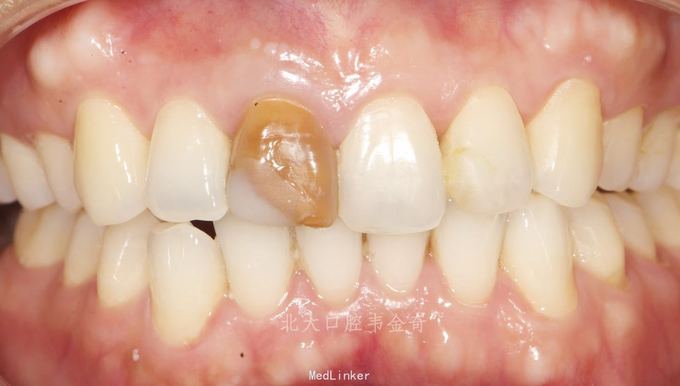

患者女,53天岁。上前牙变色,影响美观,要求治疗。既往根管治疗十余年。无不适症状。

11冠大部分面积呈深黄色,叩痛(-),不松,牙龈未见红肿。 x线片可见根充物,根尖未见异常。 12,21,22未见牙体缺损,颜色正常。